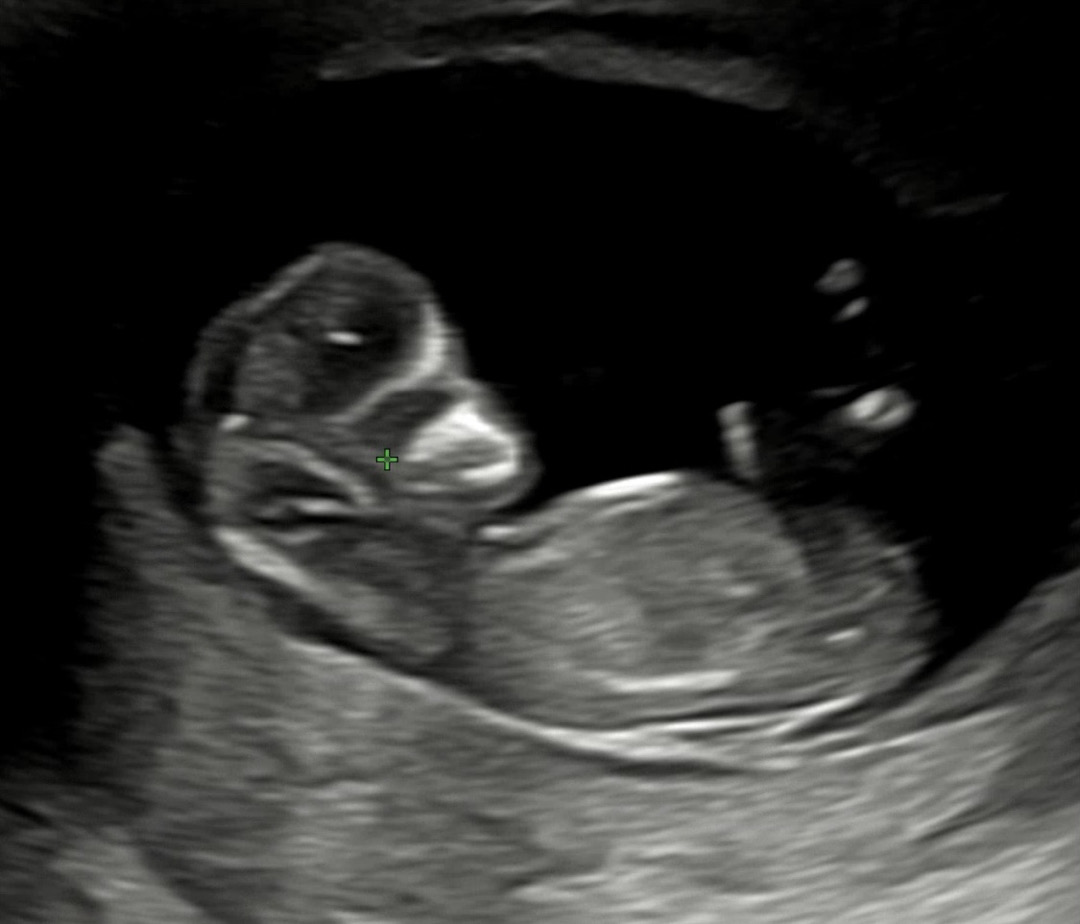

딸 같은디요?

12주차 입니다 ! 각도법고수님들 댓글 부탁드립니다 😍